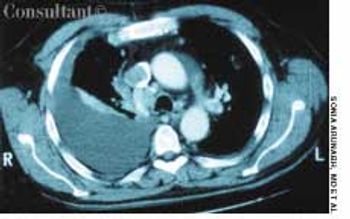

A 47-year-old man presented to theemergency department with adrooping right eye. He also complainedof a constant right-sidedheadache of 1 week’s duration; thepain involved the temporal region.Another physician had diagnosednew-onset migraine and prescribedsumatriptan, which failed to alleviatethe pain. The patient had no weakness,vomiting, or double vision.Both his father and his son hadMarfan syndrome.